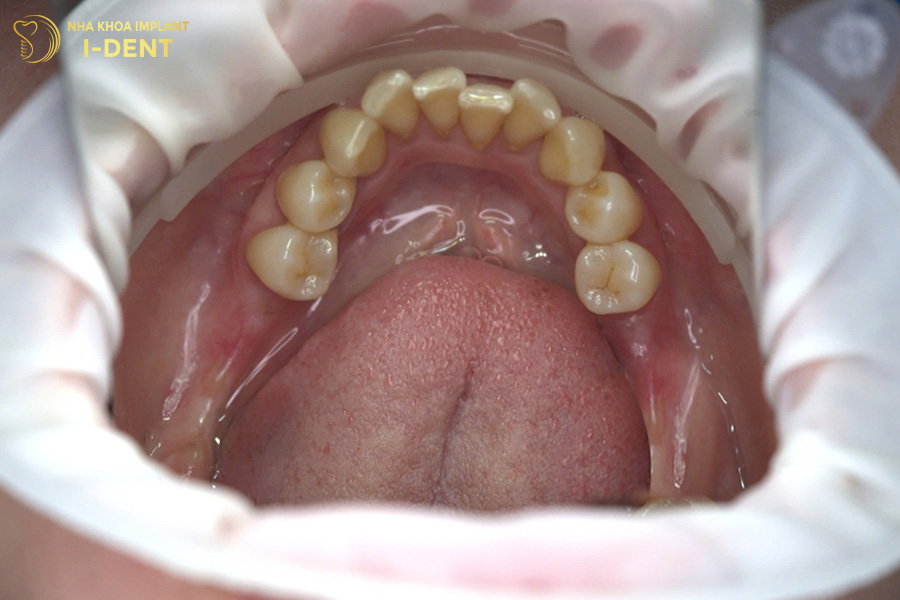

Tình trạng răng ban đầu của chú Trương Văn Sự

Nhận định đây là một tình trạng bệnh khá phức tạp, bác sĩ Đình Tín đã thăm khám kỹ lưỡng và đưa ra kế hoạch điều trị chi tiết. Đầu tiên, bác sĩ Tín chỉ định nhổ các răng lung lay, phẫu thuật ghép xương lớn tại những vị trí tiêu xương, sau đó mới tiến hành cấy ghép Implant toàn hàm All-on-4 cho chú Sự. Cuối cùng là phục hình toàn hàm với răng sứ Chrom-Cobalt (Mỹ) trên Implant cho chú.

Hình ảnh răng chú Sự sau khi cấy ghép Implant All on 4 cho hàm trên